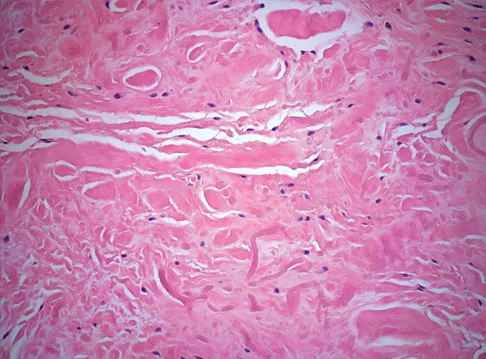

Question 13

A 55-year-old woman has slowly increasing pain at the distal end of her little finger that is exacerbated by cold temperatures. She denies any history of trauma to her hands and is employed as a school teacher. The histology of the resected specimen is shown in Figure 71. What is the most likely diagnosis?

Explanation